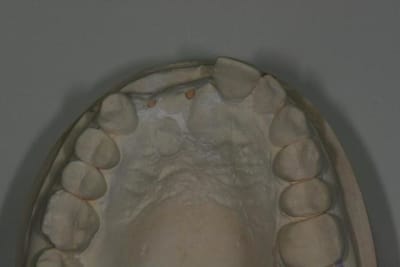

Patiente de 30 ans suite à parodontite a perdu 11-12 avec grosse perte osseuse.

Bon voila le scann de 11-12 (pas 21-22 comme noté)

C'est vrai que j'ai à mort d'os en épaisseur.

Le manque est surtout en hauteur.

Dans tous les cas je refais 21 en même temps.

Bon ben j'ai implanté avant d'avoir refait la 21. Du coup j'ai mésialé la pose de 11 pour compenser la distalisation de 21.

Au final je n'ai pas fait de greffe osseuse... et j'ai réalisé une technique de rouleau sur 11-12 mais je reste un peu court à mon goût.

J'ai mis en place des transitoires sur 11-12-21 pour temporiser 3 mois pour voir la maturation des tissus mous.